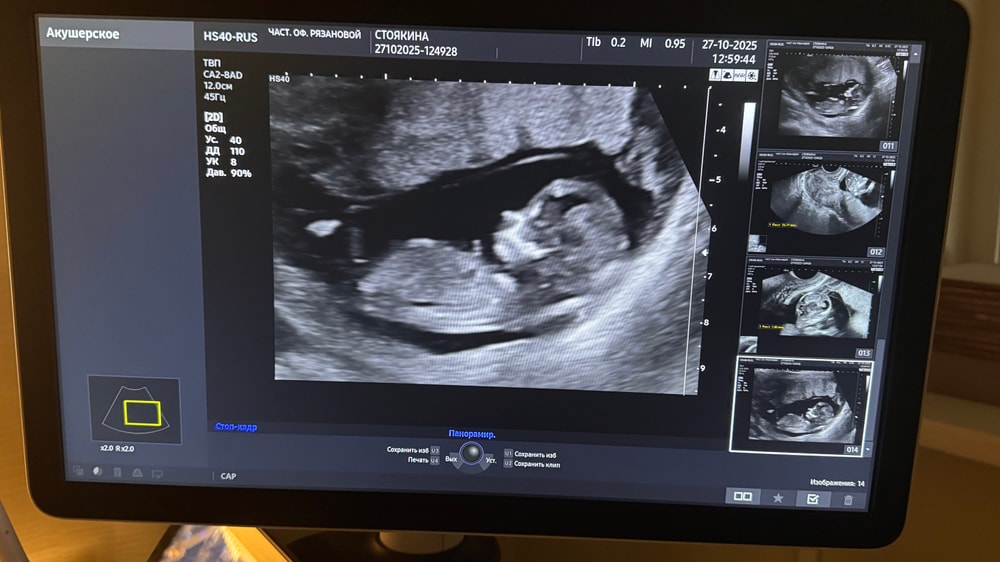

А так похоже на девочку

Таня, а как вы так поняли ?) я же правильно вижу что там половой бугорок и нет письки мальчиков ой )

Мама З сыночков и лапочки дочки , я тоже так поняла, но точно ли это этот бугорок???

У моей девчонки на узи в 12 нед, прям хорошо был виден толстый отросиочек // животику. Я врачу говорю, девочка. Она кивнула , но сказала, все равно рановато.

Как по мне - тут не видно бугорок🤷гадание на кофейной гуще. Потерпи до 15-16 недель и иди, смотри кто же в животике живёт)

Мама З сыночков и лапочки дочки , как то девочки писали по форме головки, вот мне так и видится, что мальчик.